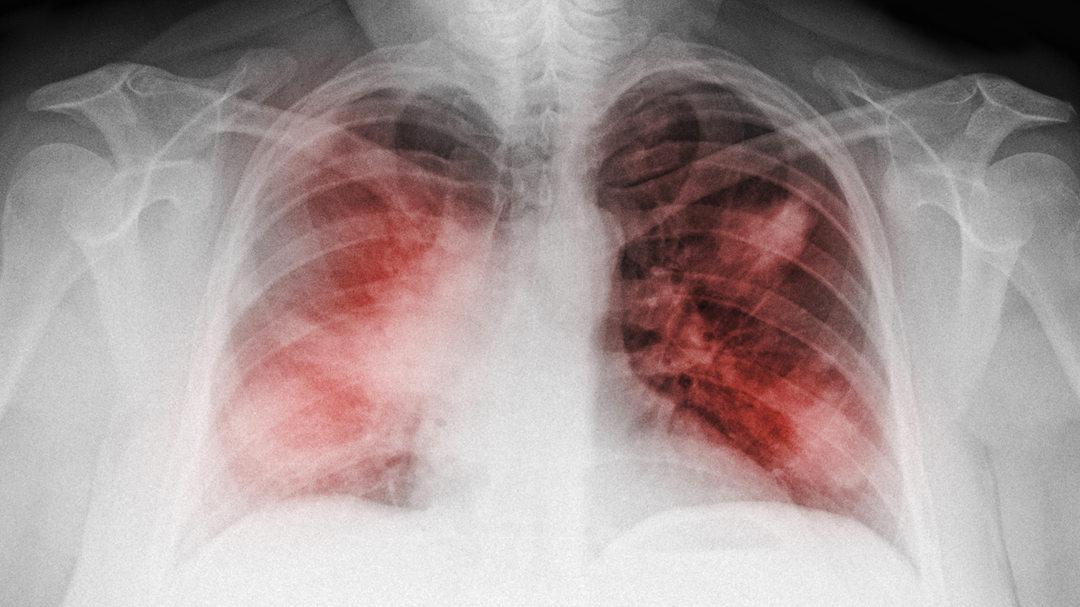

肺炎是一种常见的呼吸系统疾病,对人们的健康构成严重威胁,为了预防和治疗肺炎,及时了解自身健康状况至关重要,本指南旨在向读者详细介绍广东地区肺炎的最新检测方法及步骤,帮助大家顺利完成检测任务。